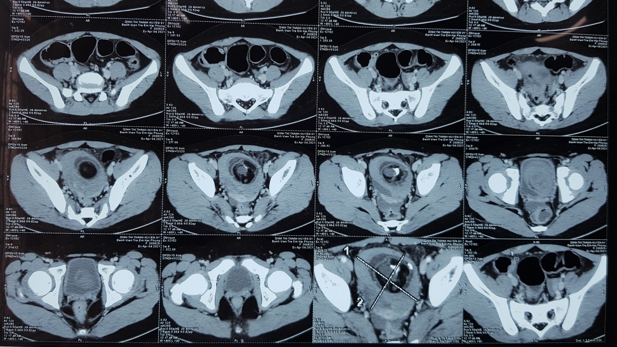

Hình 2: U buồng trứng trên phim chụp CT ổ bụng

U buồng trứng có hai loại hay gặp là u nang thanh dịch buồng trứng và u quái buồng trứng. Cả hai loại u này đều được chẩn đoán dễ dàng tại Bệnh viện Trẻ em Hải Phòng bằng siêu âm và chụp CT ổ bụng.